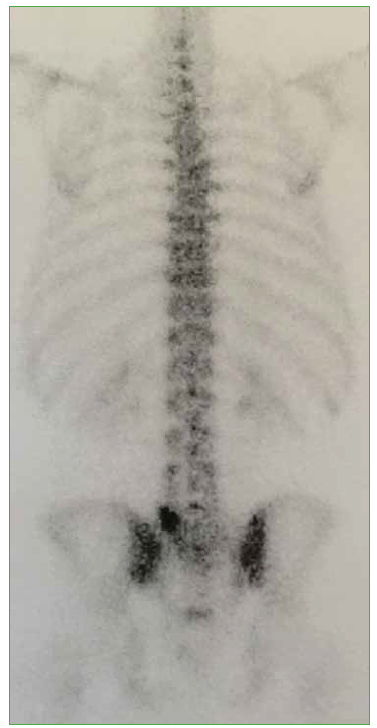

Las hernias discales intraesponjosas vertebrales o nódulos de Schmörl consisten en una herniación o una extrusión del núcleo pulposo del disco intervertebral a través del platillo vertebral hacia el cuerpo adyacente. Suelen asociarse a deformidades vertebrales, como la enfermedad de Scheuermann, o a enfermedades reumáticas, como la espondilitis anquilopoyética. En general, son hallazgos casuales y cuadros asintomáticos; son pocos los casos publicados de nódulos sintomáticos. Su aparición estaría relacionada con un platillo vertebral debilitado por traumatismo o estrés repetido. Cuando el nódulo es agudo o reciente, puede ser difícil diferenciar la degeneración benigna de una infiltración maligna o una infección. Presentamos un caso inusual de un nódulo de Schmörl doloroso en un hombre sin antecedentes de relevancia, que enmascaró una lesión metastásica de carcinoma pancreático a nivel lumbar. Se realiza una revisión bibliográfica. ABSTRACTIntraosseous disc herniation –or Schmörl nodes (SN)– are a herniation or prolapse of the nucleus pulposus of the intervertebral disc through the vertebral plate and into the adjacent vertebral body. They are usually associated with vertebral deformities, suchas Scheuermann’s disease, or rheumatic diseases, such as ankylopoietic spondylitis. In general, they are spontaneous and asymptomatic findings, and there are only a few reported cases of symptomatic nodes. The etiology is supposedly related to a weakened spinal plate due to trauma or repeated stress. When the node is acute or recent, it can be difficult to differentiate a benign degeneration from a malignant infiltration or infection. In this paper, we discuss the unusual case of a painful Schmörl node in a man with no relevant history and a masked metastatic lumbar spinal tumor originated from pancreatic cancer. We performed a literature review.Descargas